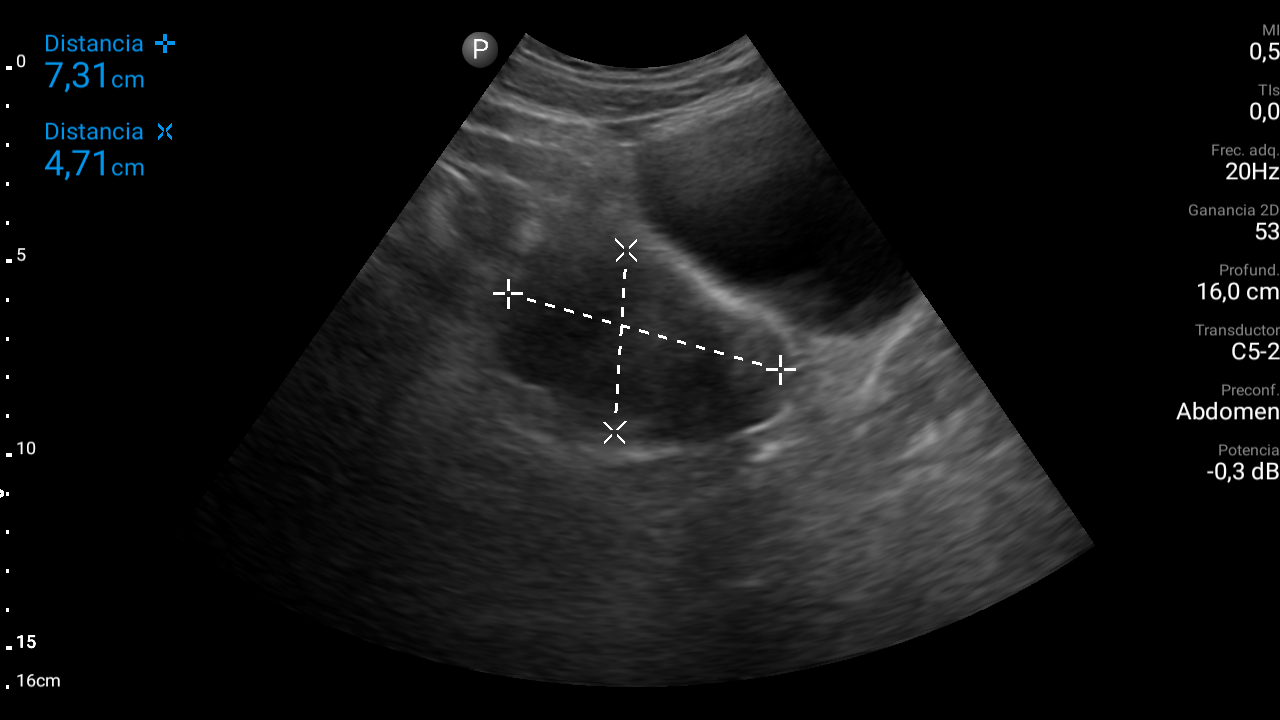

Hallazgos ecográficos

En ecografía abdominal se observa masa hipoecoica dependiente de útero por lo que se remite de forma preferente a ginecología.